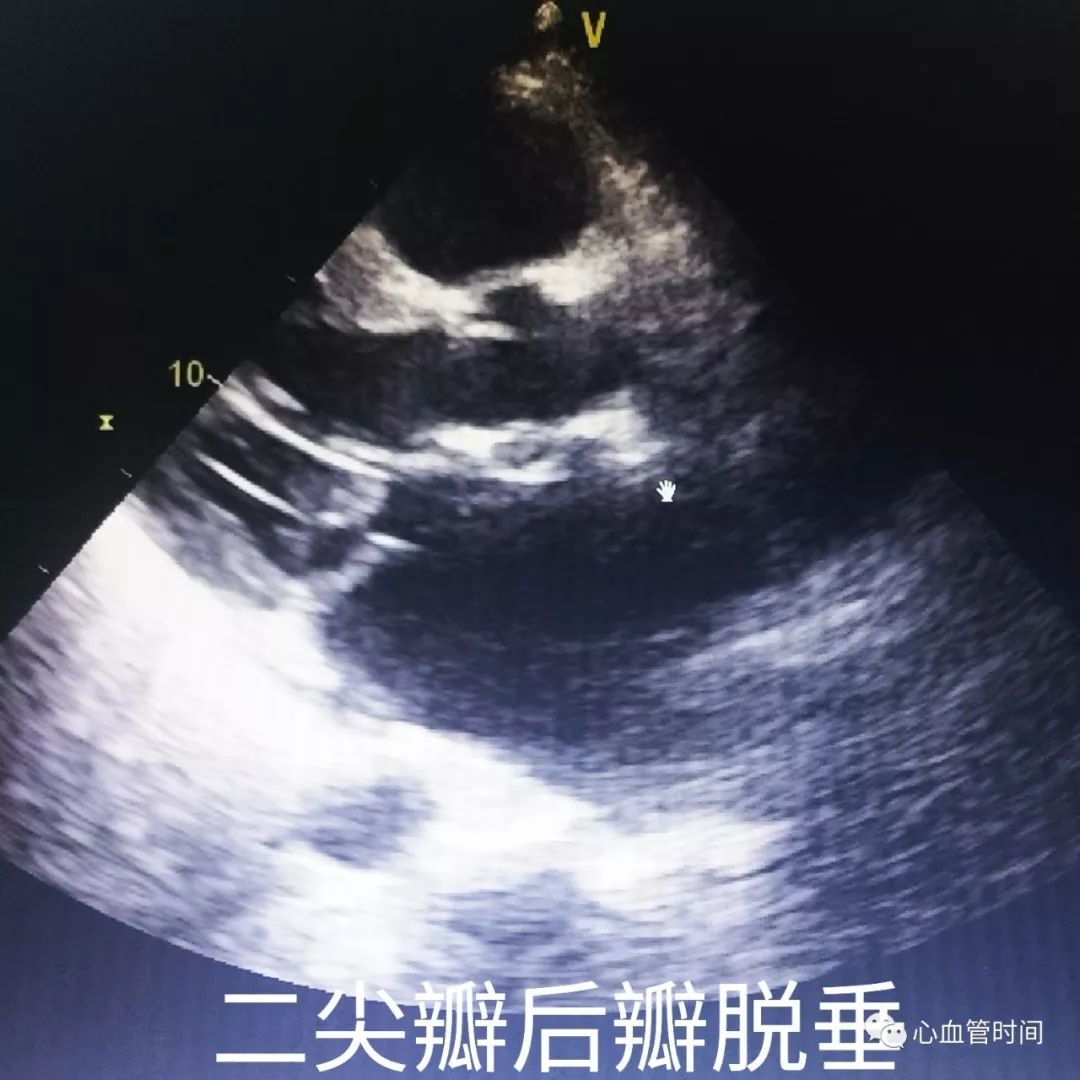

脱垂时可见

蓝色花彩血流于收缩期出现,且往往是大量

偏心性反流

。

脱垂时可见

蓝色花彩血流于收缩期出现,且往往是大量

偏心性反流

。